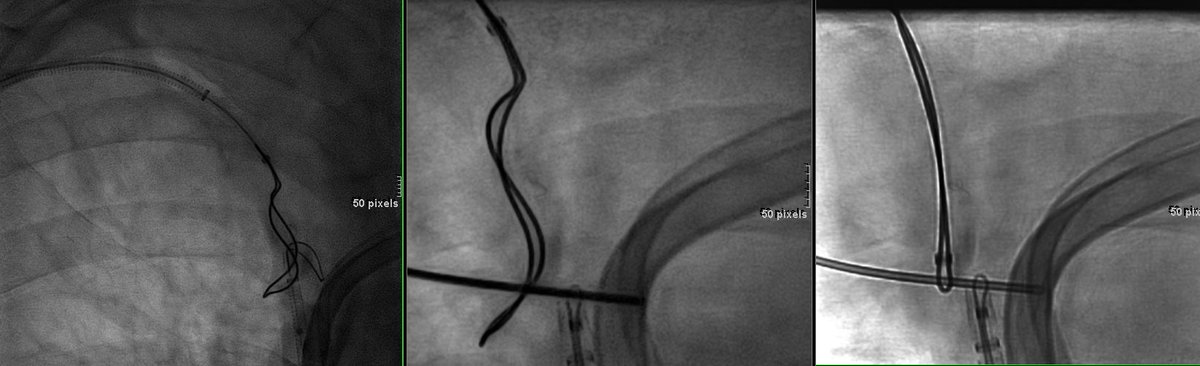

Live @MountSinaiNYC #IRad: #Gunsight recan #SVC #subclavian #twosnares @MUSCVIR @gsiskin @rkryu @amishpatelmd